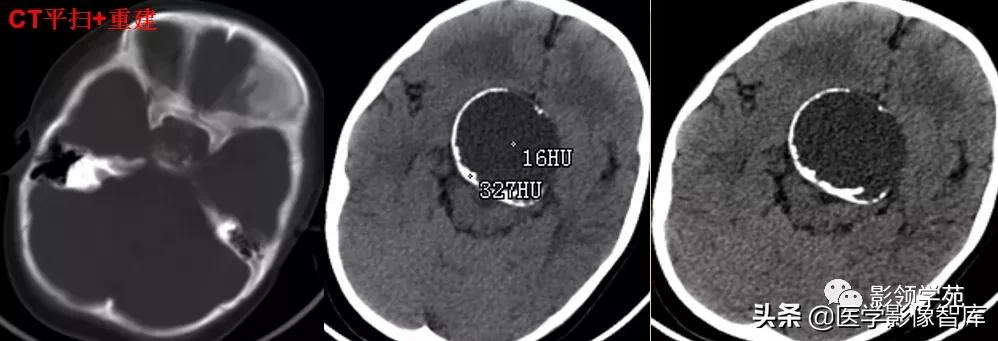

1、无血栓者:CT平扫呈稍高密度影,增强扫描呈明显均匀强化。

2、部分血栓者:CT增强扫描,中心和囊壁明显强化--靶征。

3、完全血栓者:CT平扫呈等密度影,增强时仅囊壁强化。

女 72岁,发现糖尿病3年余

鞍上区见一团块状稍高密度影,边界尚清,密度均匀。

鞍上右上方见一类椭圆形流空影。

病灶明显强化(瘤内血栓未强化),边界清楚,与右侧颈内动脉海绵段分界不清。垂体大小、形态未见异常。